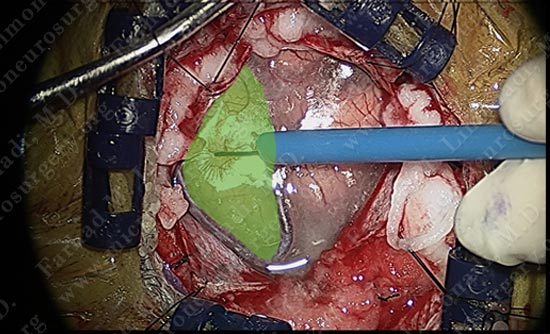

Motor cortex was identified and is colored green. The tumor is deep and within the parenchyma of this gyrus.

The superficial pole of the tumor is outlined in green.

The tumor is nicely dissected out as patient is talking to the surgeon and being examined by the surgical team.

Tumor is removed without any injury to the motor cortex or adjacent neuro-vascular structures. Patient is awake and doing well with no neurological deficit.